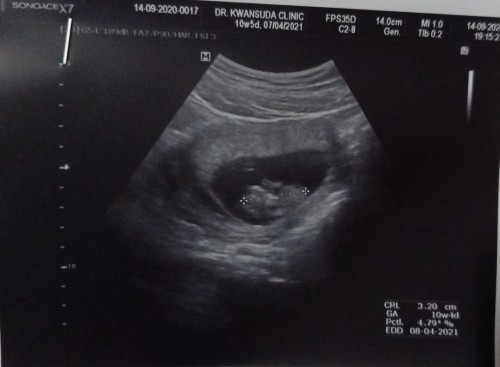

10week5dayค่ะ